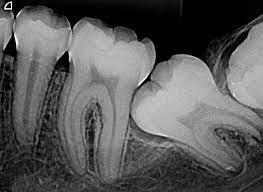

Una radiografía periapical es un tipo de imagen dental que muestra en detalle uno o dos dientes completos, desde la corona hasta la raíz y el hueso circundante. Se utiliza comúnmente para:

• Detectar caries dentales debajo de las encías.

• Observar la salud del hueso que sostiene el diente.

• Diagnosticar abscesos, infecciones o quistes.

• Evaluar el estado de los tratamientos de conducto.

• Examinar dientes fracturados o con problemas periodontales.